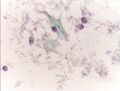

صورة مجهرية لاختبار عنق الرحم تُظهر آفة داخل الظهارة منخفضة الدرجة (LSIL) ومخاطية باطن عنق الرحم الحميد. صبغة عنق الرحم .